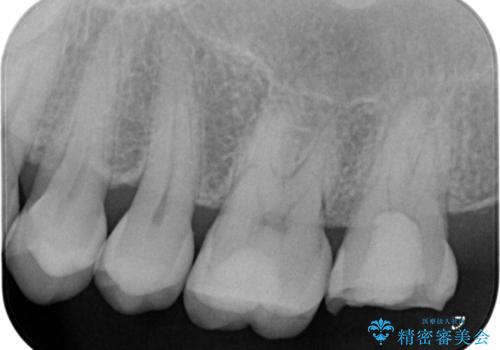

- 噛むと歯が疼いて痛い、と根管治療を希望され来院されました。

精査した結果、上顎奥歯は歯が割れてしまっており、根管治療ではなく抜歯の対象でした。

歯の抜去後、しっかりと咬合機能を回復するためインプラントを用いた治療を行っていきます。